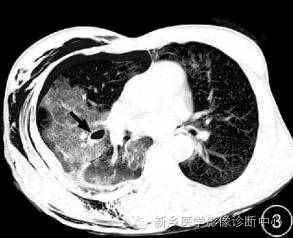

( 2) 肺气液囊: 表现为圆形或不规则形厚壁空腔,见气-液平面,表现为“杯中乳液征”, 周边见大片状密度增高影。此征象表明患者受伤程度重,肺内小血管及小气管同时损伤,血液进入囊腔所致,也可见于肺气囊的进展期; 为肺撕裂伤的最特征性表现。 医学百科网 | YxBaike.Com

( 3) 胸膜下气泡影: 表现为胸膜下、肺表面圆形或条形透亮影,多合并肋骨骨折,部分病例和肺气囊腔同时存在,多位于背侧,可能与肋骨骨折刺破胸膜或与肺泡的断裂有关, 随访复查多合并气胸或血气胸。 医学百科网 | YxBaike.Com